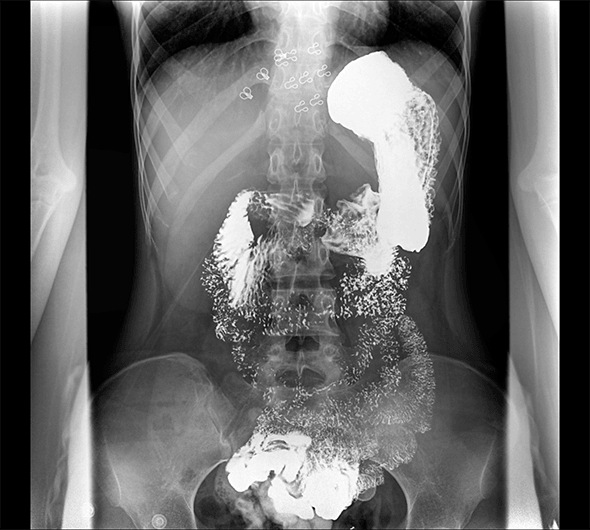

原厂优质影像链,搭载直接生长式碘化铯非晶硅平板,带来更加清晰锐利的图像效果。